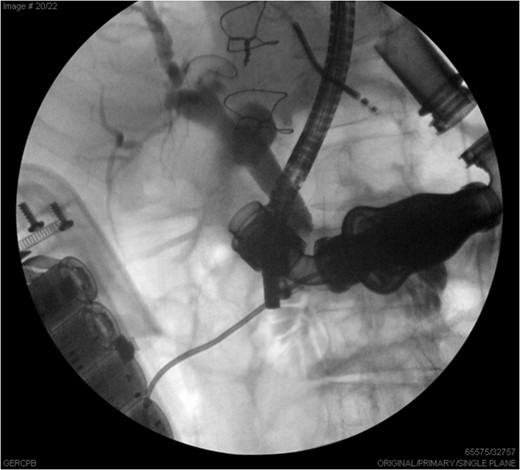

ERCP images illustrate the common bile duct with distal stricture, partially obstructed by the LVAD.